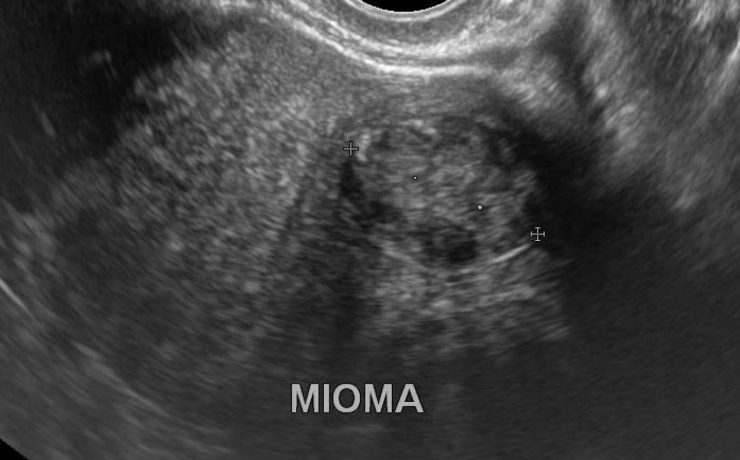

Revista Anales de Radiología de México. Ultrasonido Tiroideo en pacientes dediatricos del HIM, con diagnostico clínico de Tiroiditis de Hashimoto. México 2012 (11) – 1. Se revisaron 64 pacientes, por US más frecuente en mueres 9/1, y la lesión común es nódulo único, hipoecogénico, con contenido sólido, con vascularidad periférica.